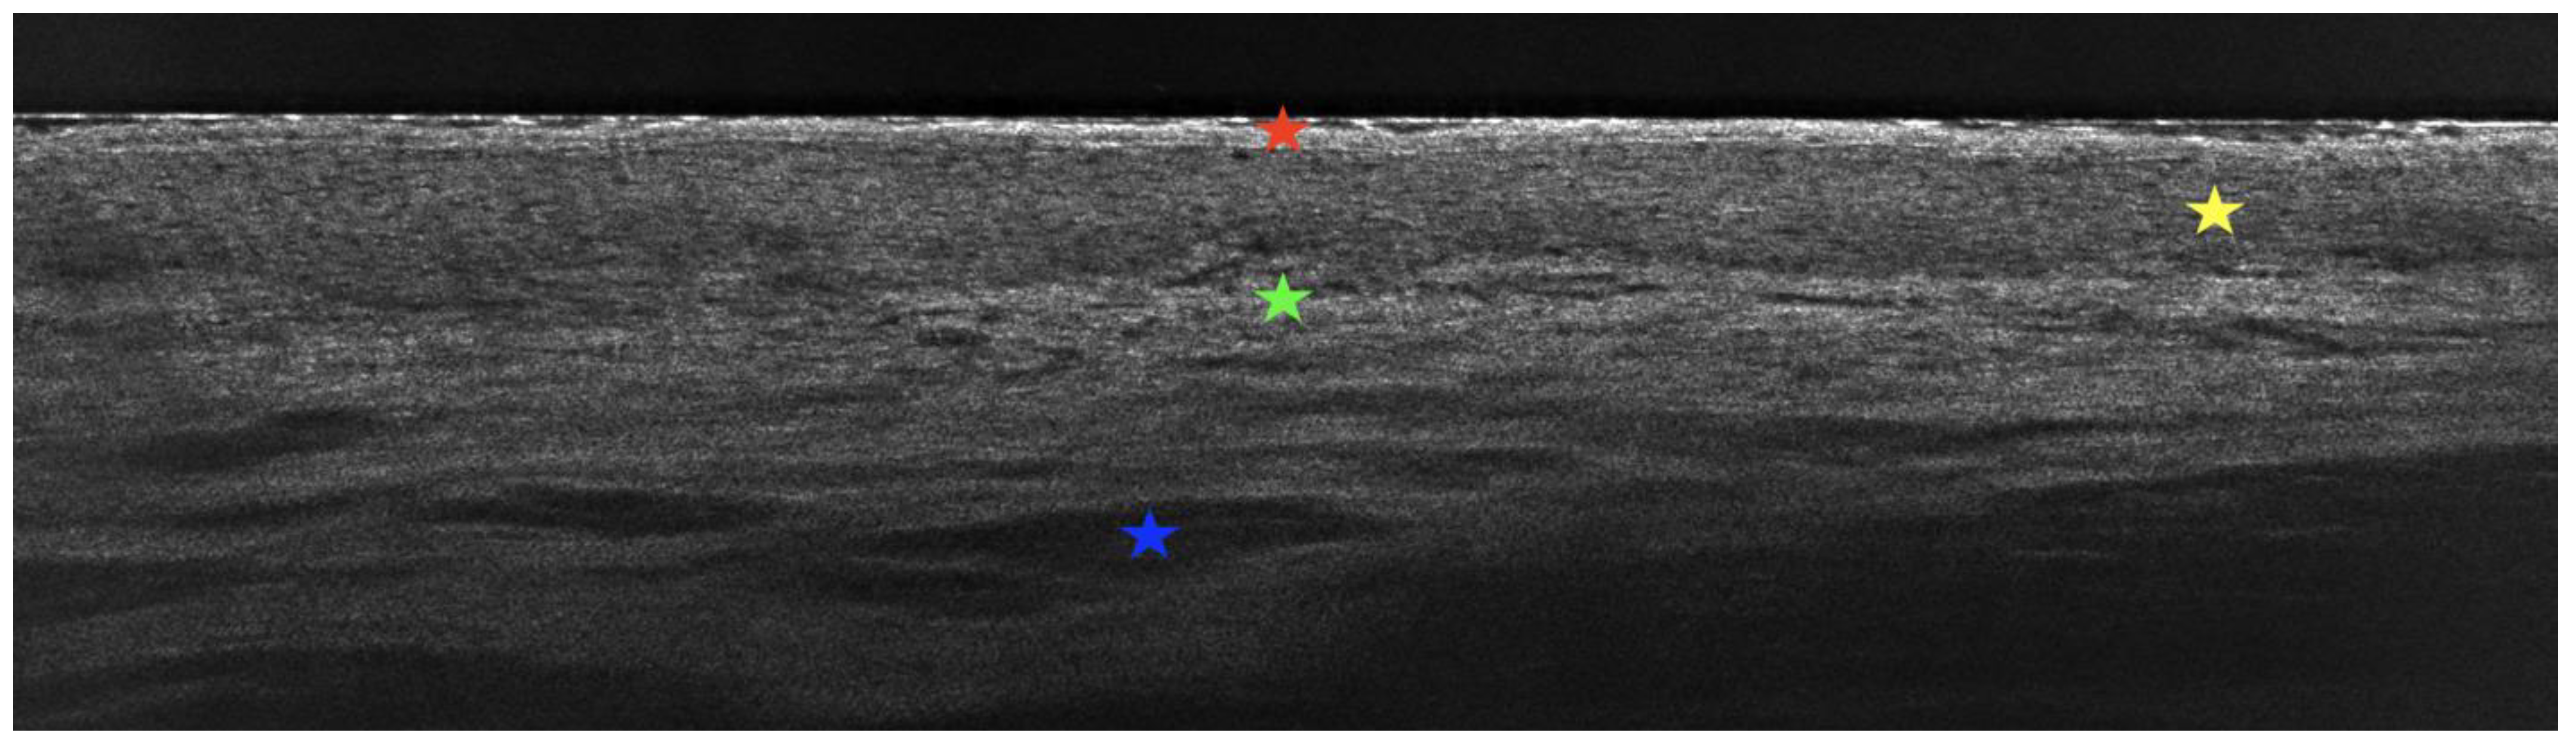

- Latriglia, F.; Ogien, J.; Tavernier, C.; Fischman, S.; Suppa, M.; Perrot, J.L.; Dubois, A. Line-field confocal optical coherence tomography (LC-OCT) for skin imaging in dermatology. Life 2023, 13, 2268. [Google Scholar] [CrossRef]

- Verzi, A.E.; Broggi, G.; Micali, G.; Sorci, F.; Caltabiano, R.; Lacarrubba, F. Line-field confocal optical coherence tomography of psoriasis, eczema and lichen planus: A case series with histopathological correlation. J. Eur. Acad. Dermatol. Venereol. 2022, 36, 1884–1889. [Google Scholar] [CrossRef] [PubMed]